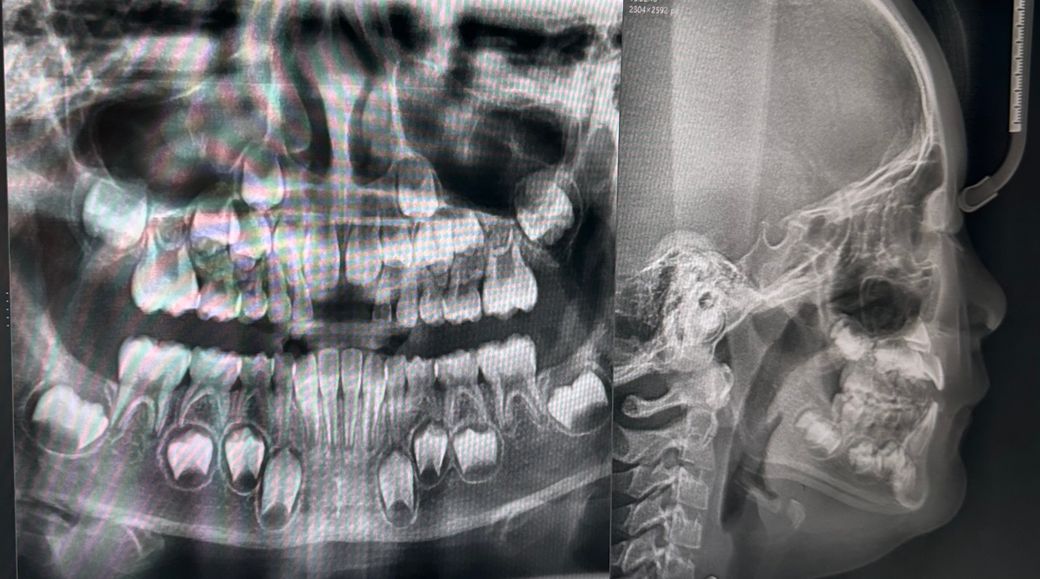

만7세 악궁장치가 꼭필요할까요?사진유

어린이 교정치과 소견은 송곳니자리가없어서 악궁장치가 필요한상황이라고합니다

치아가 나올 공간이 많이 부족해 보입니다. 일단 악궁확장을 하셔서 치아가 나올공간을 확보해주시는게 좋을것같습니다.

악궁확장이 필요할지는 가용공간, 필요공간에 대해 정확한 계측이 필요합니다 엑스레이 사진만 저렇게 봐서는 모르고요